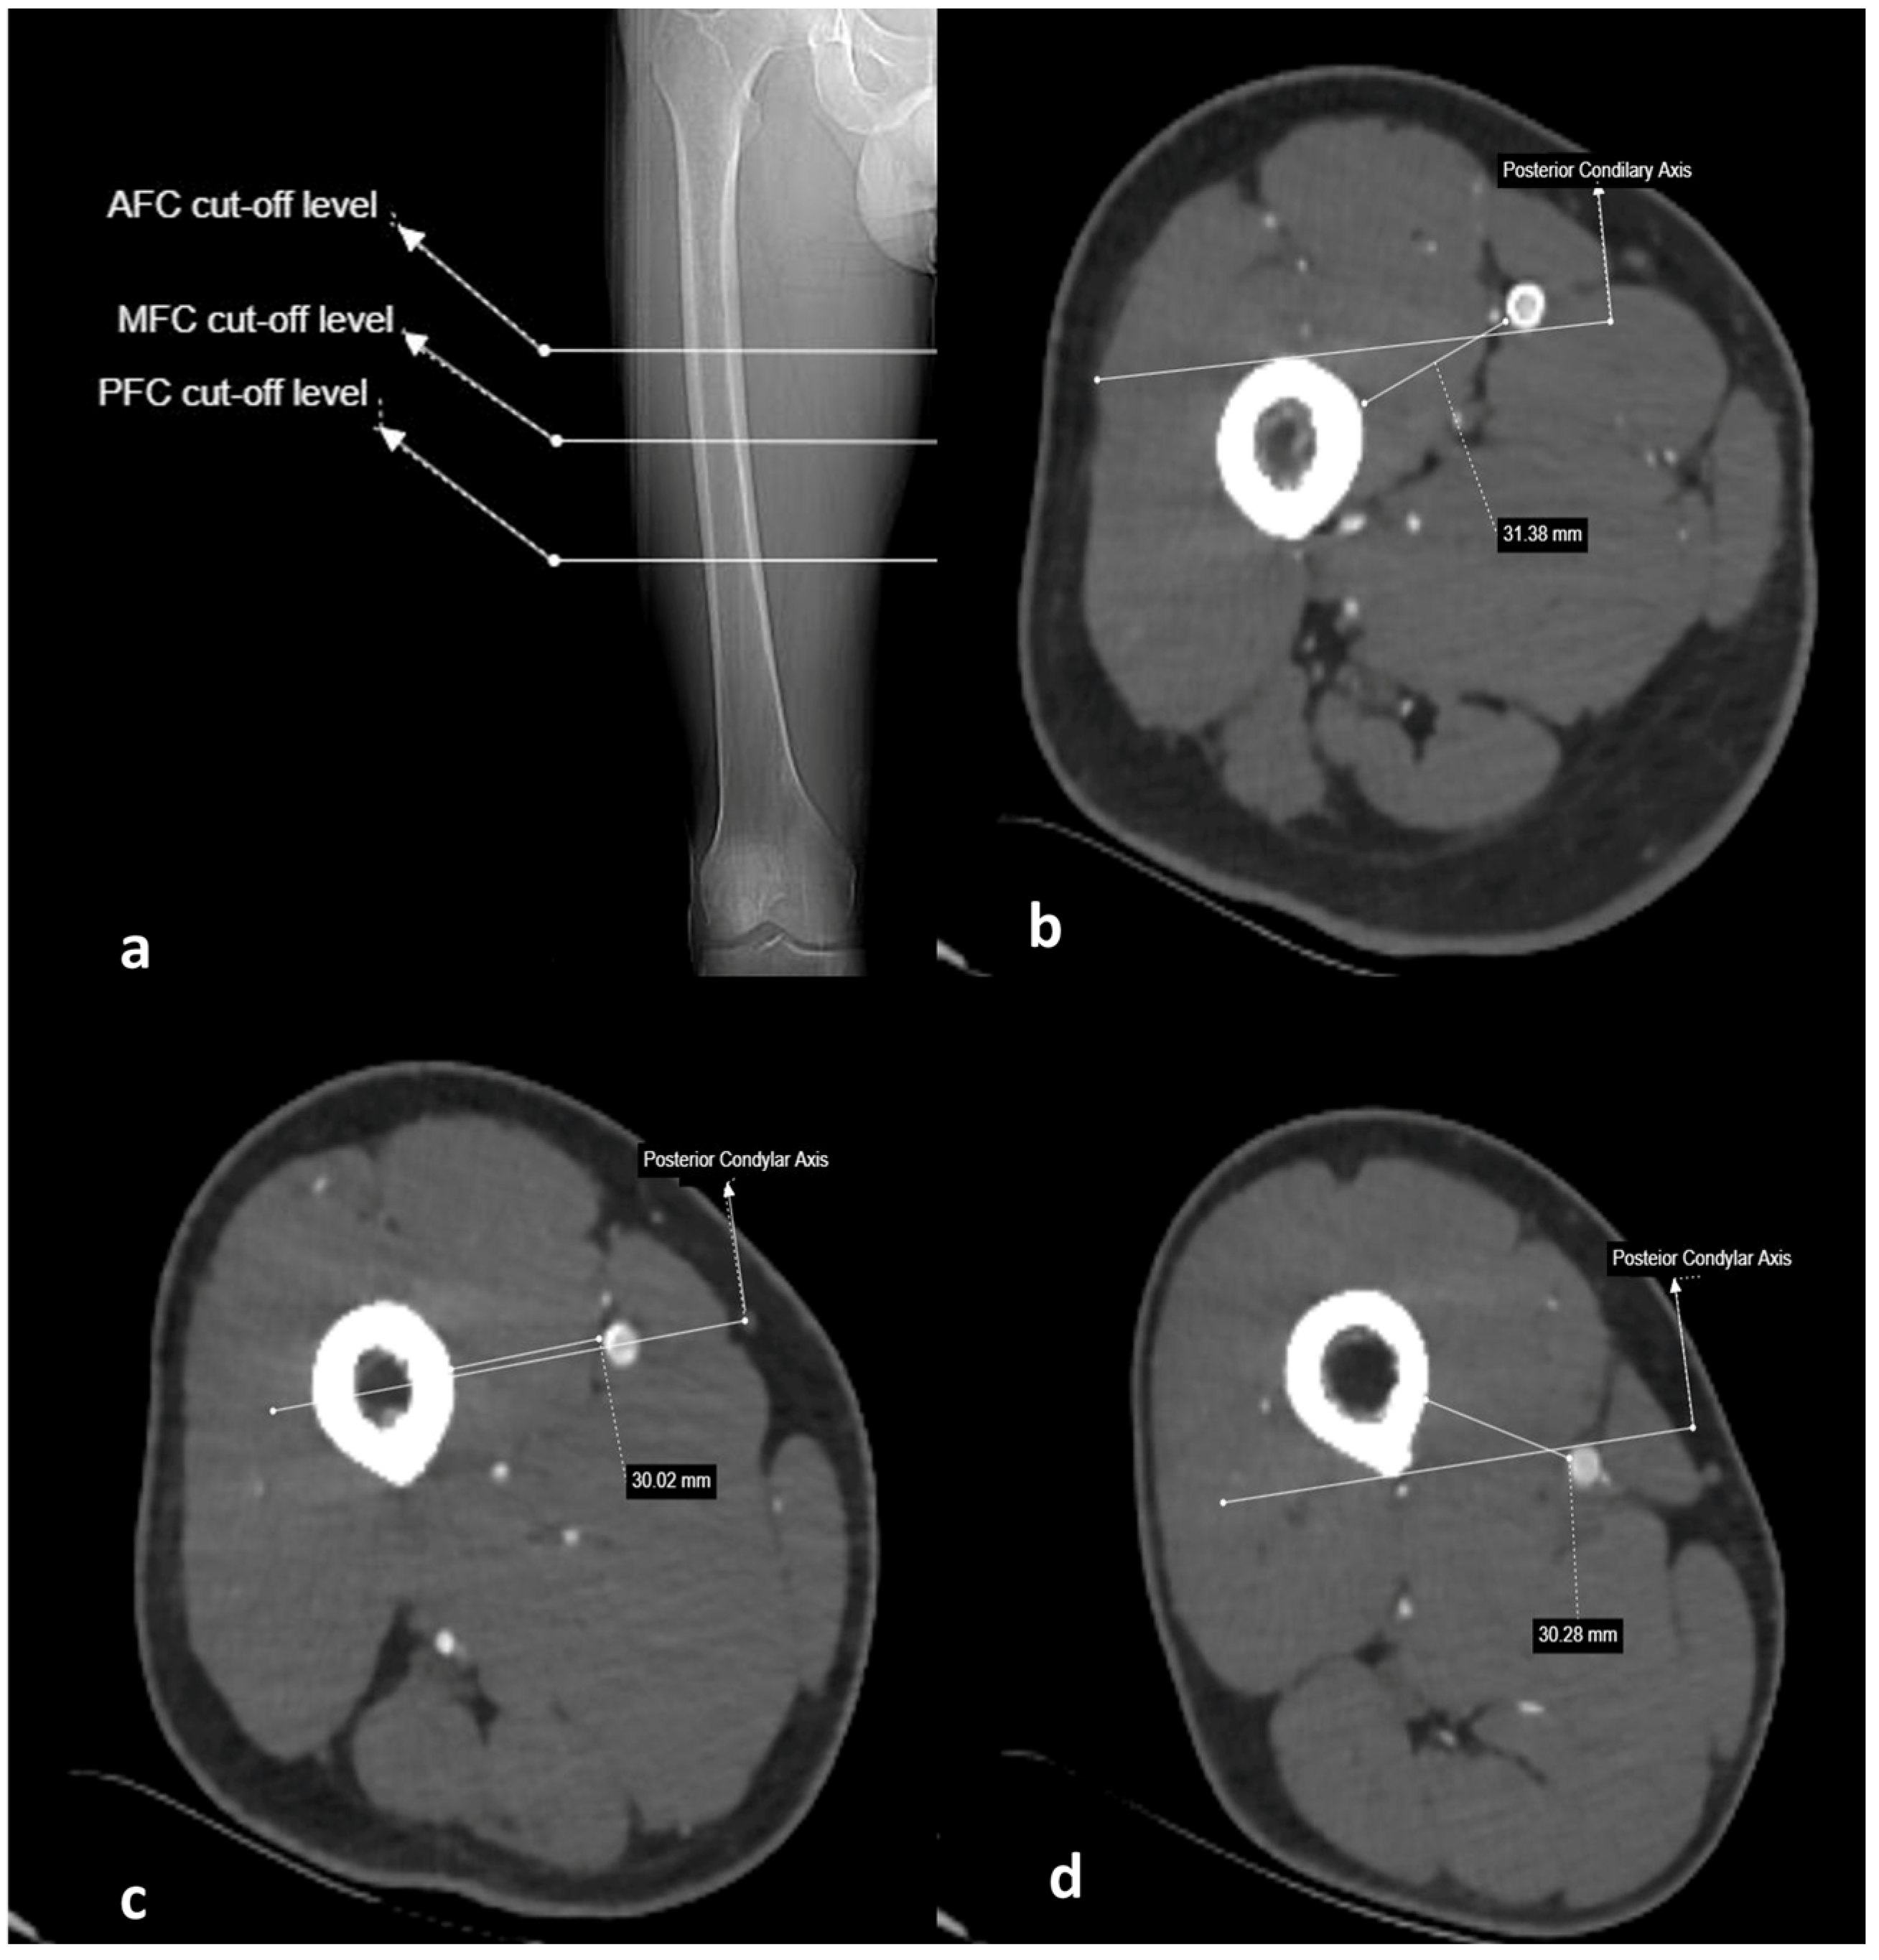

2.3. Imaging and Measurement Methods

| Anterior femoral cortex | 223.01 ± 27.38 (156.3–293.8) | 265.04 ± 28.21 (207.0–334.5) | 27.20 ± 5.32 (15.1–40.4) | 16.49 ± 9.94 (−9.7–40.5) |

| Midsagittal femoral cortex | 180.78 ± 26.83 (107.1–246.3) | 222.40 ± 27.65 (156.1–292.6) | 25.22 ± 5.52 (11.5–58.2) | NA |

| Posterior femoral cortex | 128.01 ± 29.59 (54.1–200.1) | 170.13 ± 29.96 (93.9–241.7) | 22.93 ± 6.04 (7.6–38.0) | −36.58 ± 11.30 (−79.2–−10.3) |